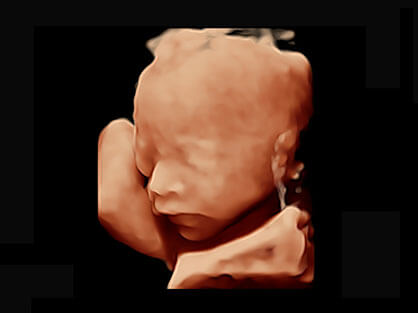

自动获取标准切面,自动完成测量,帮助医生快速完成检查,同时提升测量准确性。

宽频带腹部凸阵探头和腹部容积探头、大角度腔内探头和腔内容积探头、独特的生殖专用曲柄探头,为妇产应用提供全面诊疗方案。

卵泡结构的自动识别和测量,可显示多组测量数据。